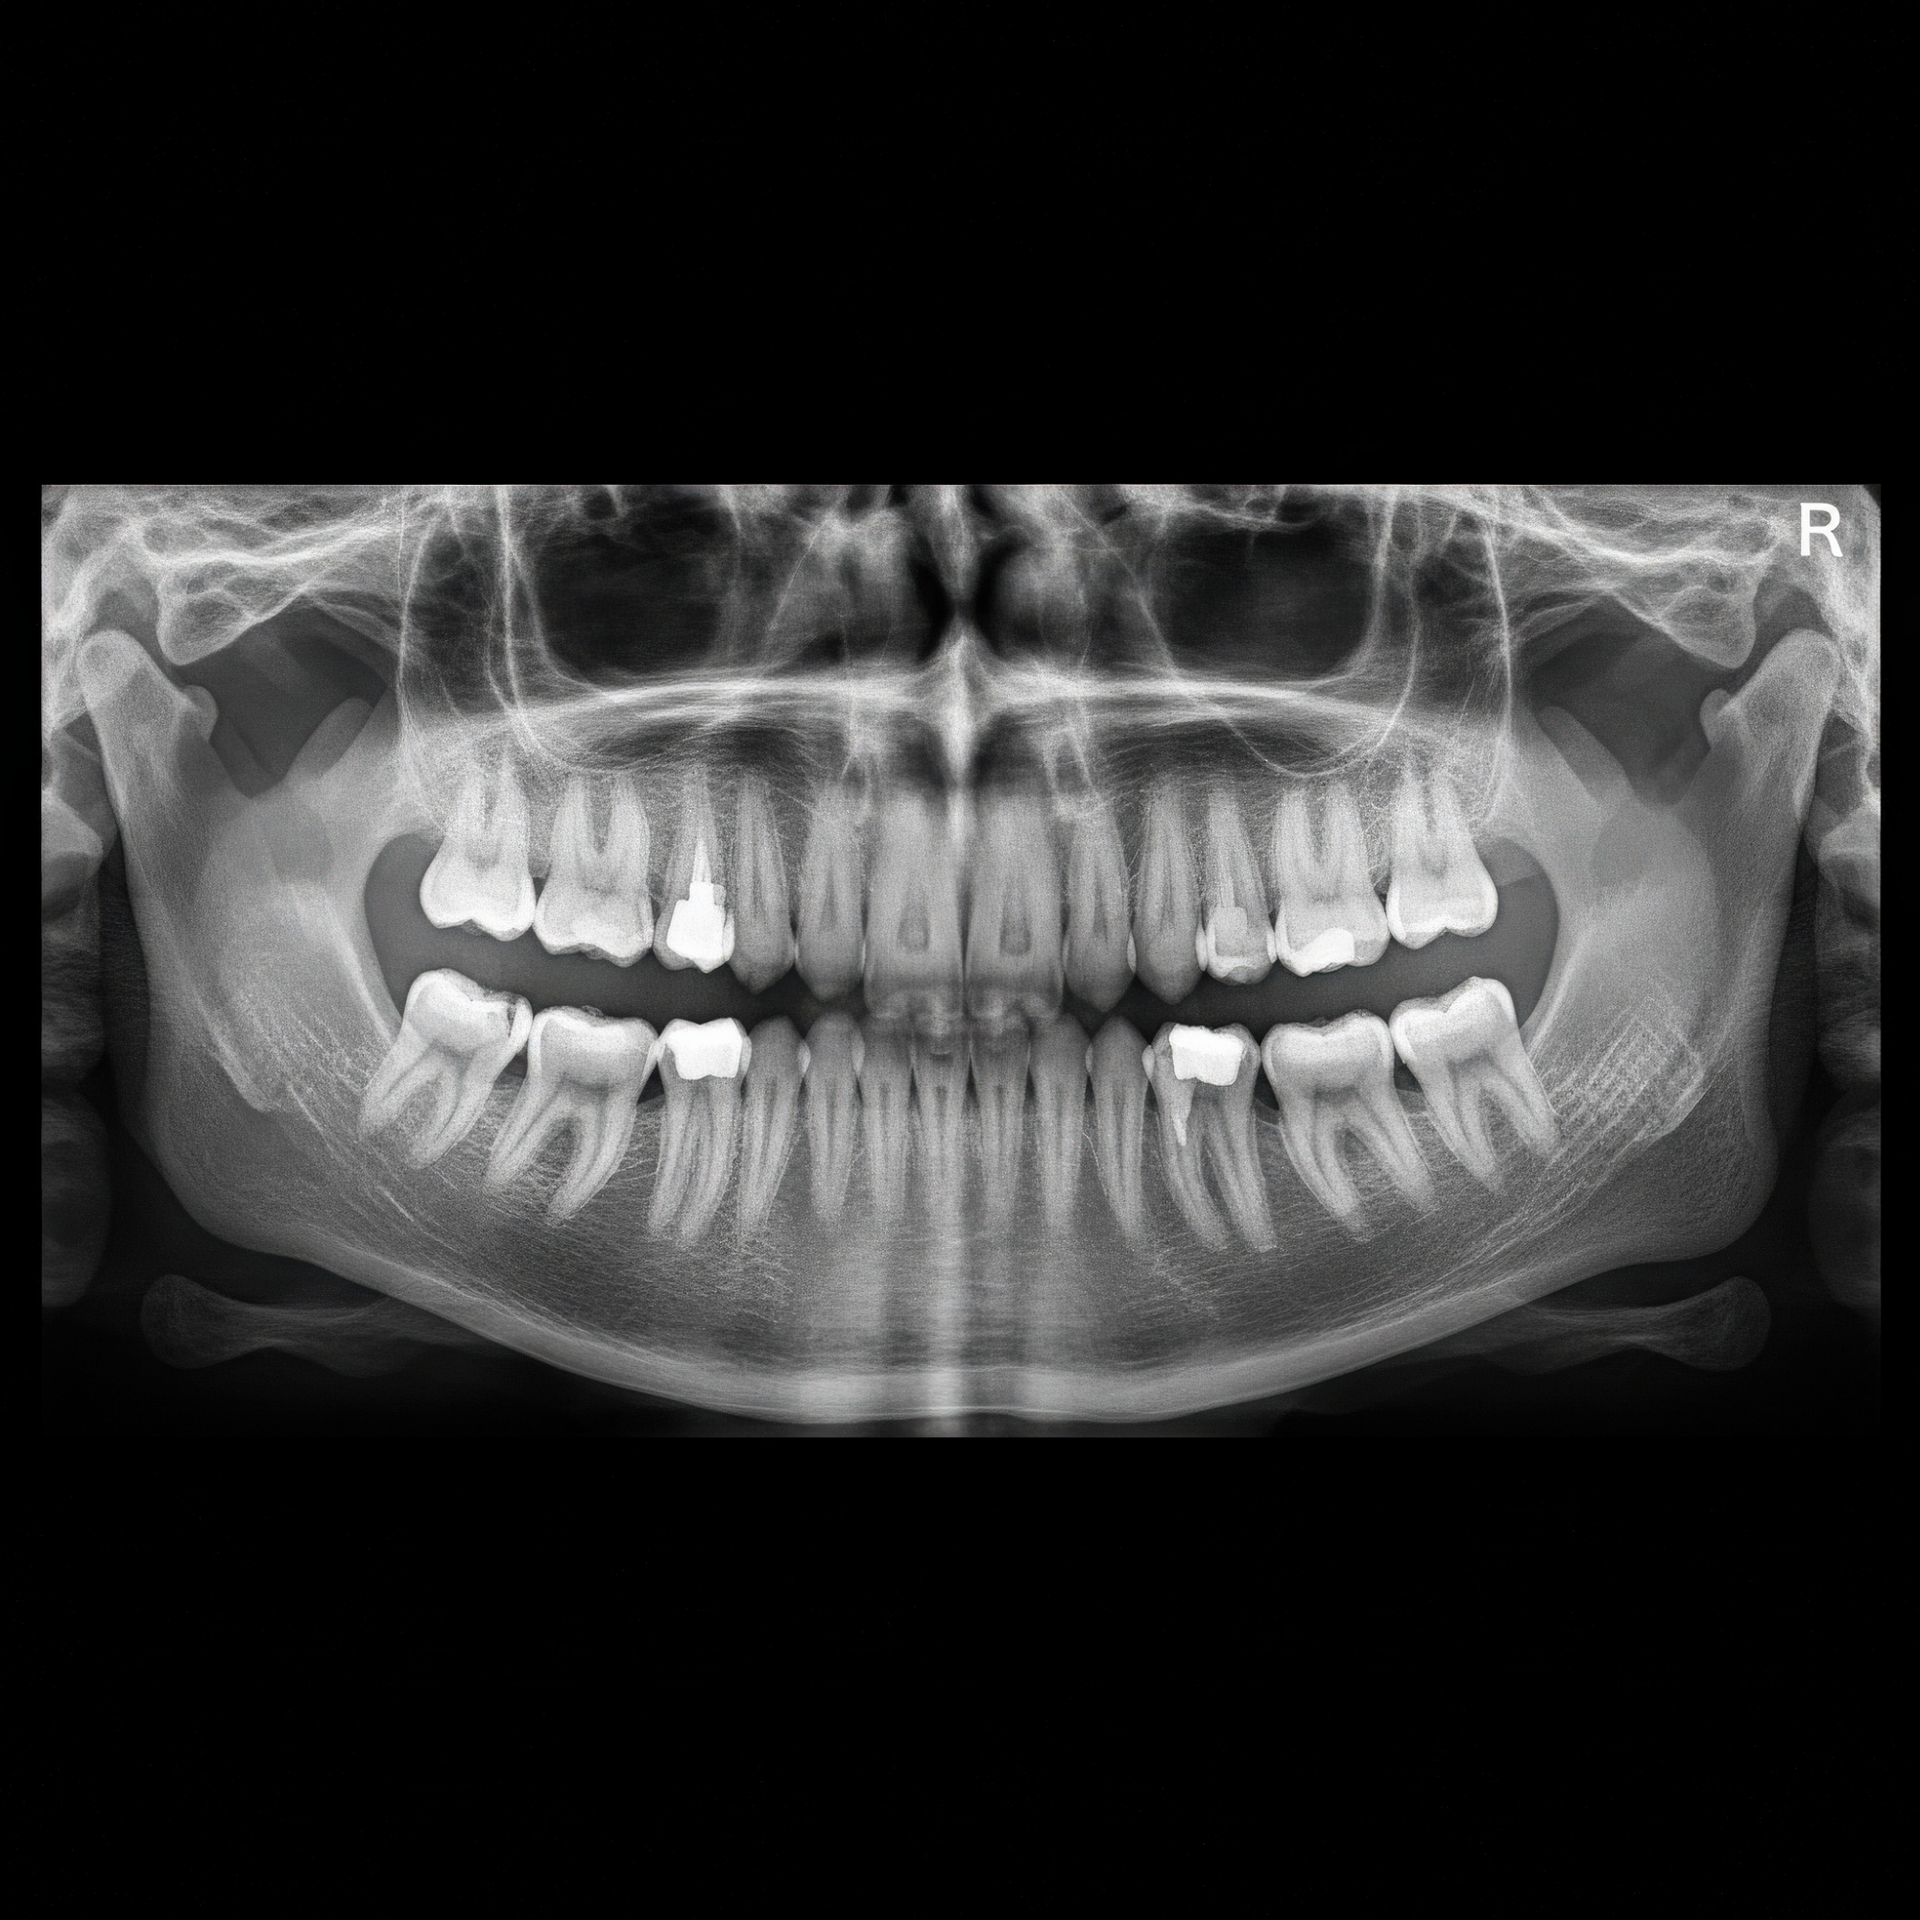

Equipo profesional de radiografías panorámicas: Obtiene la mejor calidad de imagen con la menor dosis de radiación y le garantiza un resultado perfecto.

- Las radiografías digitales pueden producir imágenes de muy alta calidad, gracias a las cuales su odontólogo puede observar la su estructura dental escaneada con mucha precisión, tales como: pequeñas lesiones, evaluar cambios periodontales, diagnosticar lesiones periapicales y caries proximal, evaluar la reabsorción radicular externa y cambios óseos alrededor de implantes, entre otros.